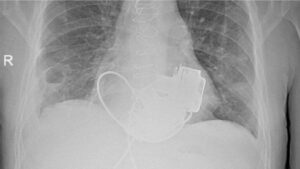

Por primera vez, en Rusia se implantaron de manera simultánea dos ventrículos cardíacos artificiales —izquierdo y derecho— a un paciente de